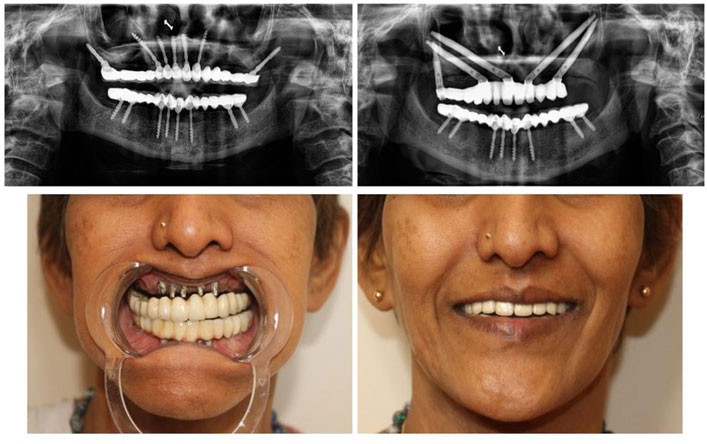

Full Mouth Implants in Kolkata

Full mouth implants are a comprehensive solution for replacing all missing or severely damaged teeth. Using dental implants as a foundation, a full set of artificial teeth is placed to restore function and appearance.

The procedure can take several months, as it involves multiple stages, including healing time for the implants to integrate with the bone.